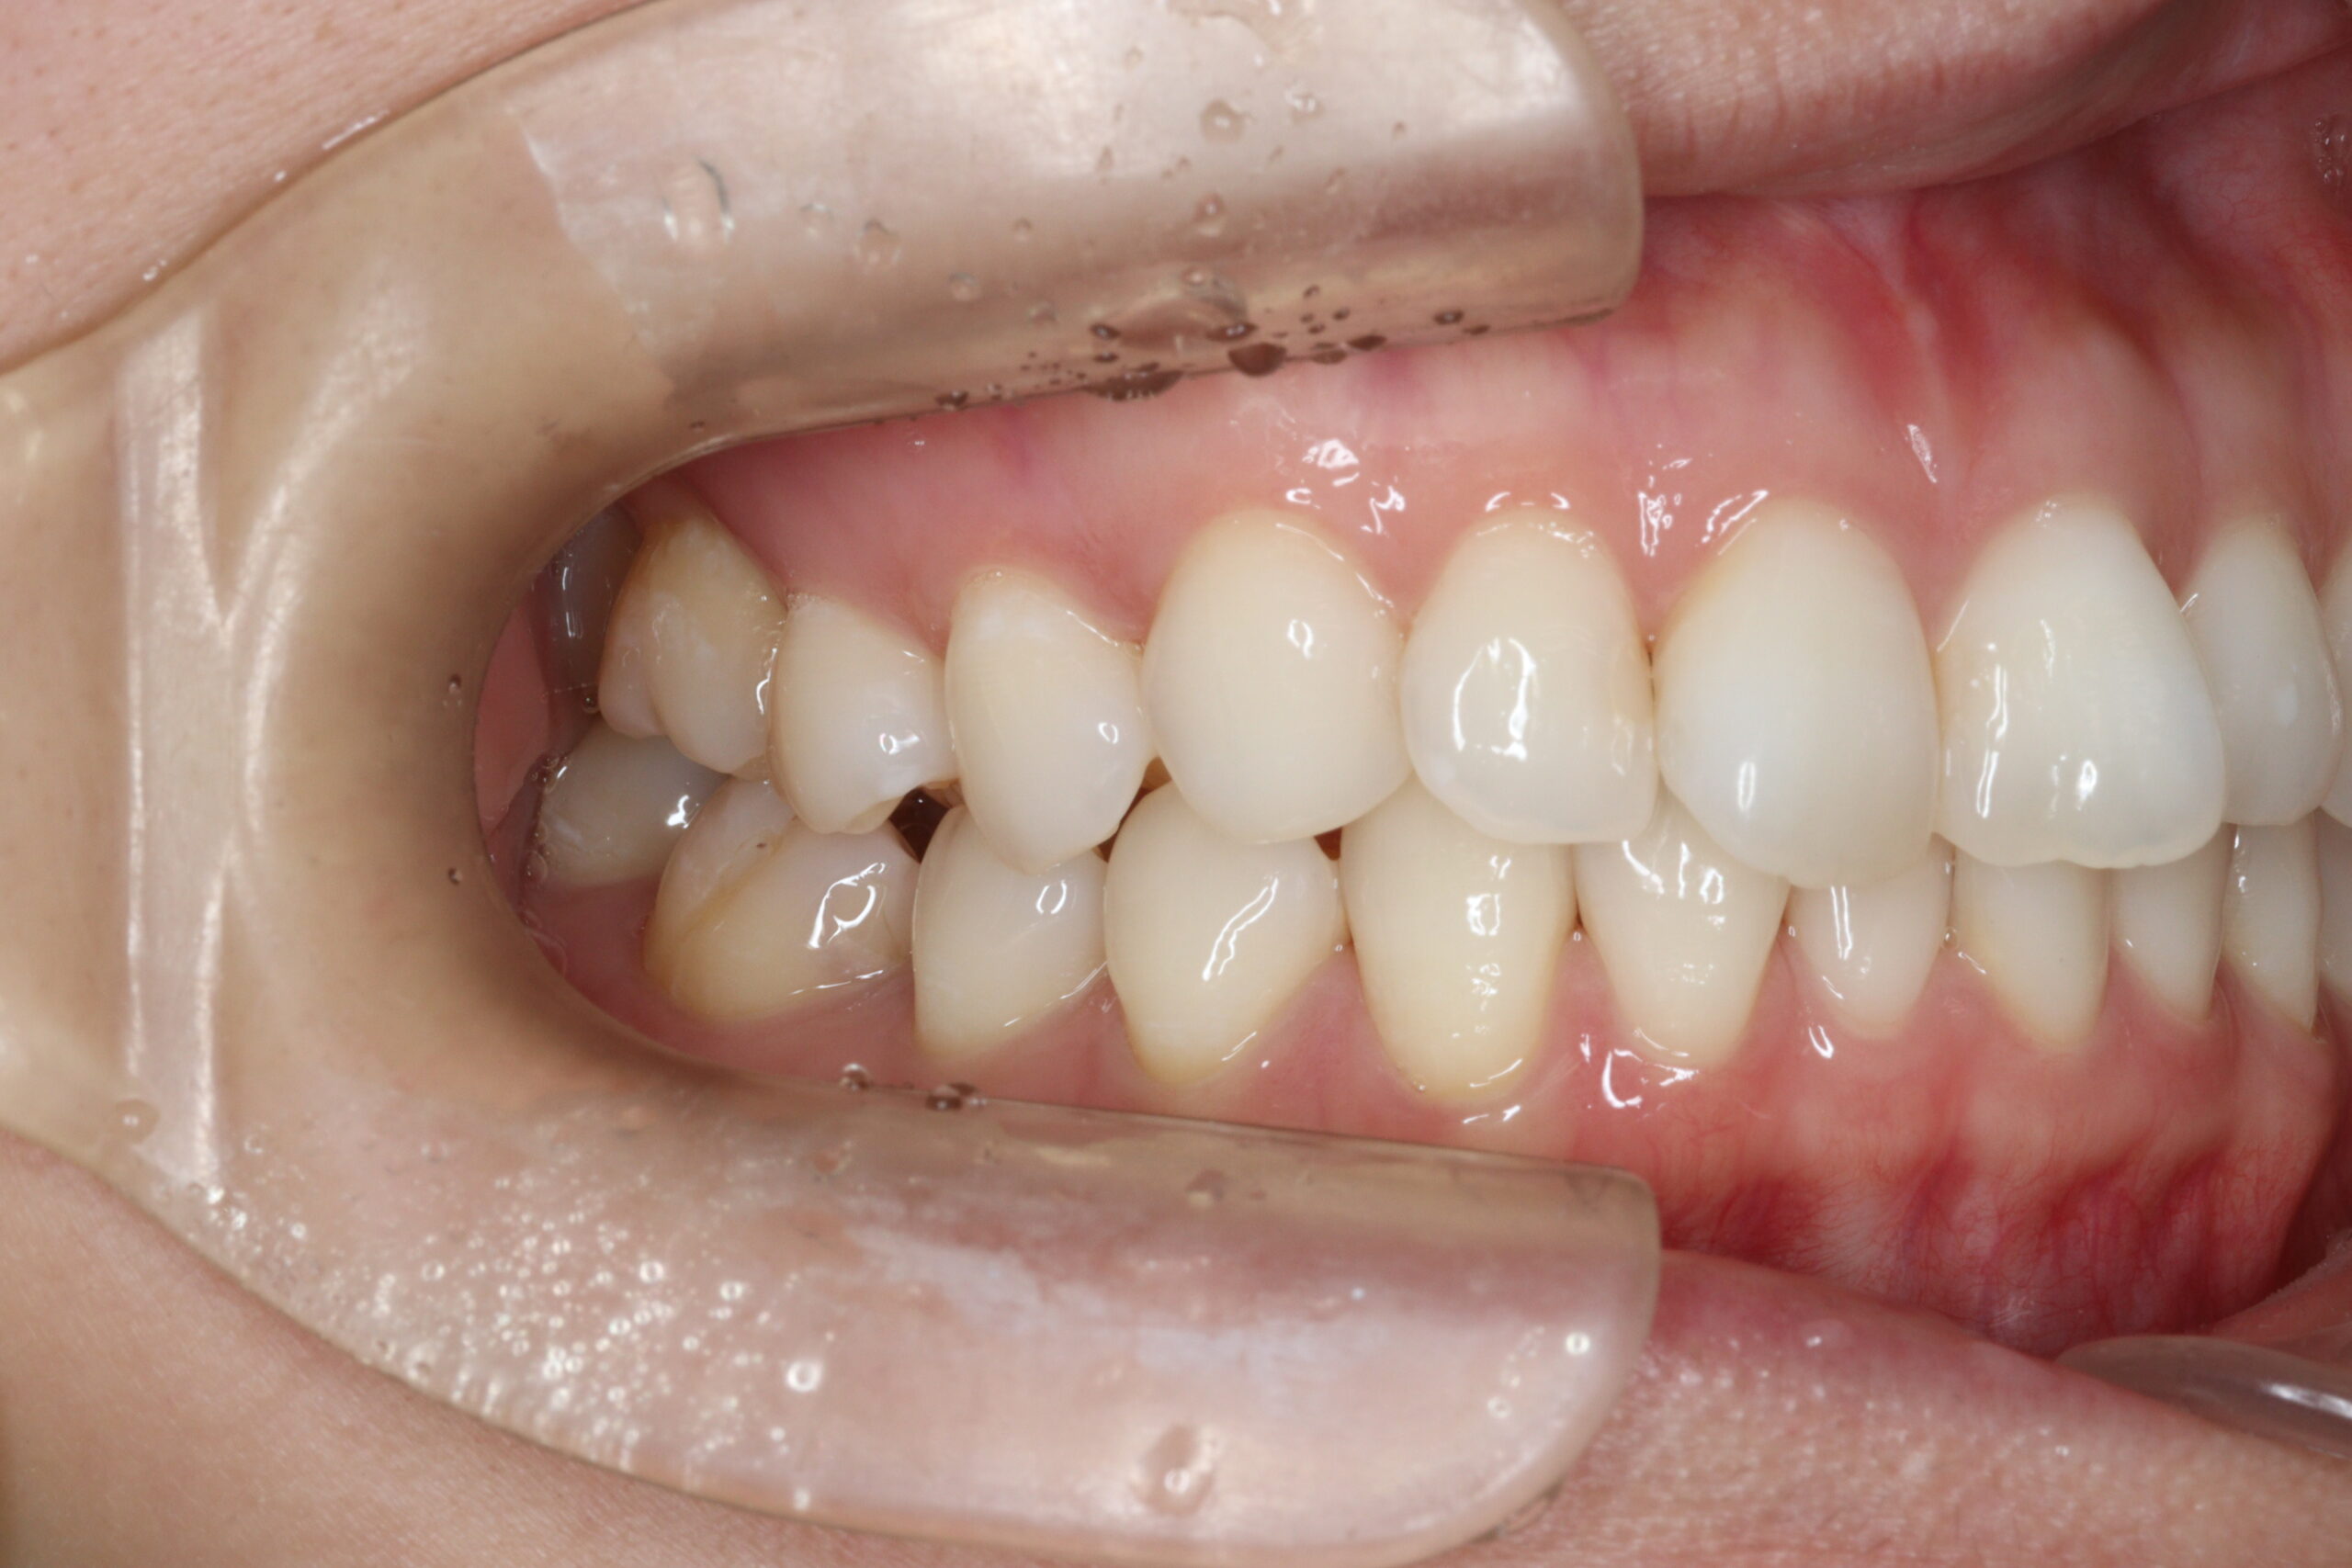

矯正術前:右側

矯正術後:右側